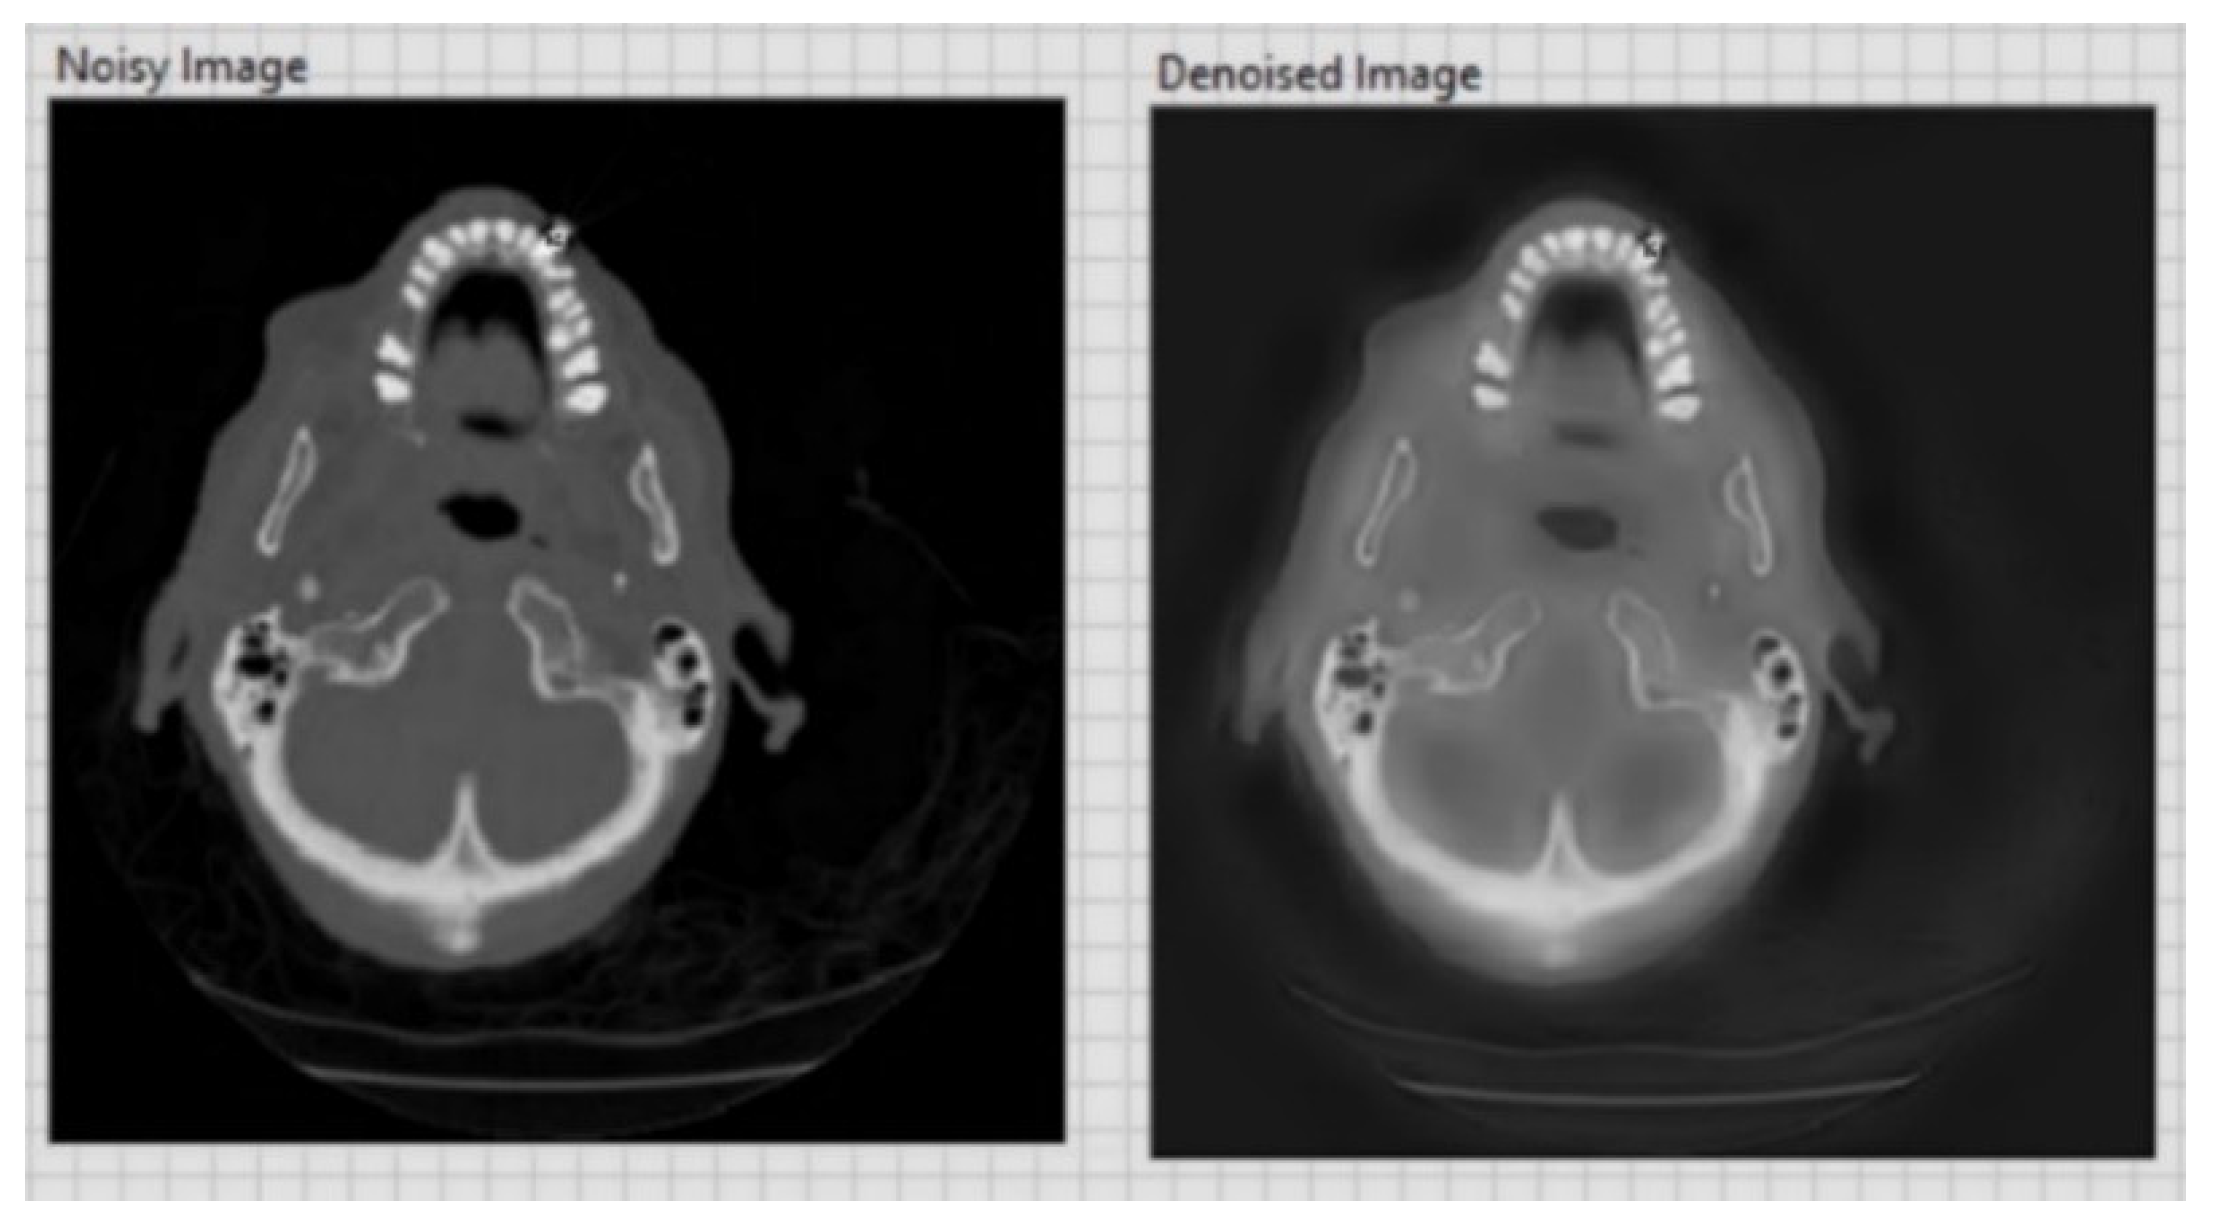

- Improving image quality by selectively eliminating disturbing information, such as noise, and eliminating other defects caused by the acquisition device by using adaptive filters.

| CT image (Figure 6) 256 × 256 | 26.01 | 0.05 |

| CT image (Figure 7) 256 × 256 | 20.15 | 0.1 |

| CT image (Figure 8) 256 × 256 | 20.13 | 0.1 |

| CT image (Figure 9) 256 × 256 | 26.09 | 0.05 |

| CT image (Figure 10) 256 × 256 | 20.18 | 0.1 |

| CT image (Figure 11) 256 × 256 | 26.15 | 0.05 |